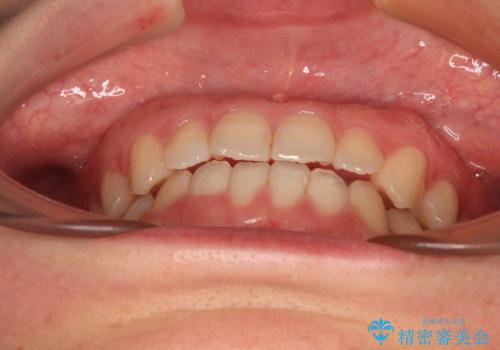

前歯のクロスバイト インビザラインによる矯正治療

- 前歯のクロスバイトとデコボコを気にして来院された患者様です。

骨格的に下顎前突傾向であるため、自己管理が煩わしくないようであれば、インビザラインによる矯正治療がお勧めとなります。

インビザラインを用い、下顎歯列を後方に移動させながら全市の被蓋を改善し、歯並びを整えていくこととしました。